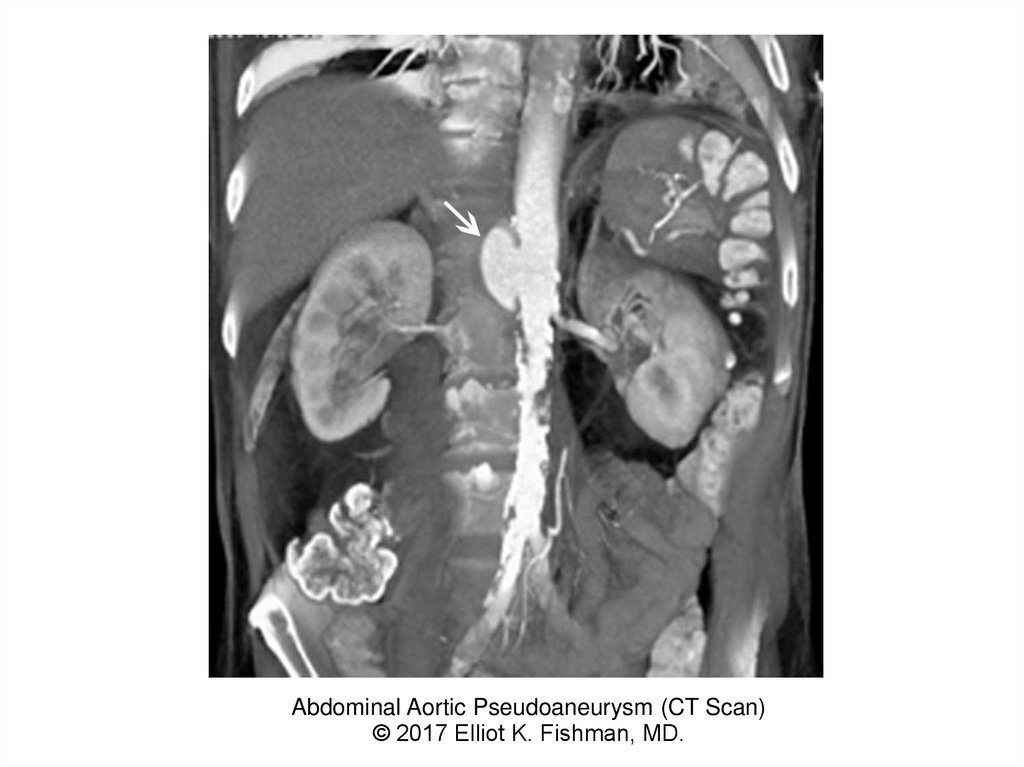

Abdominal Aortic Pseudoaneurysm (CT Scan)

© 2017 Elliot K. Fishman, MD.